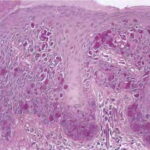

PATHOLOGY The intraepidermal adenocarcinoma of EMPD and MPD has a similar histologic appearance. There are groups, clusters, or single cells within the epidermis that show nuclear enlargement with atypia, prominent nucleoli, and well-defined ample cytoplasms . Intercellular bridges are absent. The cells can be within all levels of the epidermis and can compress but preserve the basal layer without junctional nest formation. The cells can extend into the contiguous epithelium of hair follicles and sweat gland ducts. Acanthosis, hyperkeratosis, and parakeratosis are often present. These cells have a “pagetoid” appearance and simulate other intraepidermal malignancies, including melanoma, pagetoid squamous cell carcinoma in situ, mycosis fungoides, cutaneous adnexal carcinomas (sebaceous carcinoma, porocarcinoma, and others), Merkel cell carcinoma, Langerhans cell histiocytosis, and other epidermotropic cutaneous metastases. The cells of MPD and EMPD can be pigmented, which should not necessarily indicate they are melanocytic. Paget's cells have intracellular mucopolysaccharides, with EMPD having a greater amount of mucin as compared

Immunohistochemistry is a useful adjunct in making the correct diagnosis. Low-molecular-weight cytokeratin stains cytokeratin 7 (CK7) and anti-cytokeratin (CAM 5.2) are sensitive markers for both MPD and EMPD . They are not completely specific, however, with both Toker and Merkel cells showing CK7 positivity. The cells of MPD and EMPD may stain with carcinoembryonic antigen and epithelial membrane antigen. The most useful keratin markers for Paget disease are CAM 5.2 and CK7, as they stain more than 90 percent of Paget's cells but do not react with epidermal or mucosal keratinocytes.13,14 The cells of pagetoid squamous cell carcinoma in situ typically do not stain with CK7 and CAM 5.2. S100 and HMB-45 are useful markers to exclude melanoma, as both are typically negative in MPD and EMPD. CK20 positivity has been found more frequently in cases of secondary EMPD with underlying carcinoma as compared to those cases of primary intraepithelial EMPD (CK7+/CK20-).15 Gross cystic disease fluid protein-15 (GCDFP-15) is a marker for apocrine epithelium and is typically positive in primary EMPD not associated with underlying neoplasm. In contrast, GCDFP-15 is frequently negative in those cases of secondary EMPD with an associated malignancy.16 Mucin core protein (MUC) expression is useful in the diagnosis of MPD and EMPD.17 MUC1 positivity is noted in both MPD and EMPD. MUC2 expression is generally negative in primary EMPD, but may be expressed in those cases of secondary EMPD with an associated underlying gastrointestinal adenocarcinoma. MUC5AC is frequently positive in primary EMPD and less commonly noted in secondary EMPD or those cases of primary intraepithelial EMPD that becomes invasive. SPECIAL TESTS Diagnosis of MPD and EMPD should be accompanied by a thorough search for underlying malignancy. Mammography is indicated in all cases of MPD, with biopsy of any underlying breast mass. In cases of EMPD, workup is directed toward the possibility of an underlying gastrointestinal or genitourinary neoplasm. Imaging of the abdomen and pelvis, colonoscopy, barium enema, cystoscopy, intravenous pyelogram, chest x-ray and mammogram (for the rare association of EMPD and MPD), and blood work are appropriate tests. Some reports have suggested that positron emission tomography scans may be useful for cases of invasive EMPD to evaluate for lymph node involvement and metastases. COMPLICATIONS Failure to identify and adequately treat cases of MPD can lead to metastatic disease with a poor prognosis. EMPD, if left untreated, can become invasive with a less favorable outcome. PROGNOSIS AND CLINICAL COURSE Overall survival in patients with MPD is affected by lymph node status and the presence of an underlying breast mass. Patients with negative lymph nodes have been shown to have a 10-year survival rate of 75 percent to 95 percent, whereas those with positive lymph nodes have a survival rate of 20 percent to 45 percent.4 Patients with a palpable breast mass have a 5-year survival probability of 35 percent to 51 percent, as compared to 75 percent to 82 percent in patients without a palpable mass. The prognosis for primary EMPD confined to the epidermis is excellent with appropriate treatment. Careful monitoring for early detection of local recurrence is critical given the multifocal pattern often present in EMPD. In contrast, invasive EMPD has a high rate of metastasis and carries a poor prognosis. The depth of invasion appears to be an important prognostic factor, with microscopic invasive disease (less than 1 mm) having a more favorable prognosis as compared to those with deeper invasion. Lymphovascular invasion and regional lymph node metastases markedly reduces overall survival rate and indicates a very poor prognosis. Clitoral EMPD has been shown to have a higher incidence of death from the disease as compared to other vulvar EMPD locations. In cases of secondary EMPD, the prognosis is related to the underlying carcinoma. TREATMENT Mammary Paget Disease Treatment of MPD is surgical. However, optimal surgical management of MPD remains to be defined, and treatment choice is frequently based on the presence or absence of an underlying breast mass. Mastectomy remains the standard definitive treatment. However, evidence suggests that MPD treated with breast-conserving surgery results in local control and survival rates similar to those achieved with mastectomy. Proper preoperative imaging is required to rule out multi-focal disease that would make breast-conserving therapy less effective and favor mastectomy. Lymph node evaluation via axillary dissection or sentinel lymph node biopsy must be considered in MPD. Adjuvant therapy with radiation, chemotherapy, or hormonal therapy is recommended based on lymph node status and specific features of the primary tumor. All diagnoses of MPD require referral to a physician with expertise in the management of breast cancer. Extramammary Paget Disease EMPD has been treated with a variety of different modalities. Although surgical management of the disease is the most frequently used method, various other treatments have a role for non-surgical candidates and as adjuvant therapy. SURGERY Surgery remains the treatment of choice for EMPD when tolerated by the patient. However, high local recurrence rates are seen after standard surgical excision, even with wide margins. This is most likely due to the irregular margins, multi-focal nature of the condition, and subclinical involvement of apparently unaffected skin. Several reviews have shown an overall recurrence rate of up to 44 percent with wide local excision, The local recurrence rates are higher in cases of invasive disease as compared to those limited to intraepithelial involvement. In addition, more radical and extensive surgeries are associated with lower rates of local recurrence. Patients with primary vulvar EMPD treated with radical vulvectomy, radical hemivulvectomy, and wide local excision have reported recurrence rates of 15 percent, 20 percent, and 43 percent, respectively. Multiple scouting biopsies to help delineate the extent of the disease before surgery can be a useful adjuvant technique.26 Intraoperative staining with CK7 is the preferred immunostain for intraoperative tissue evaluation.27 Sentinel lymph node biopsy has been described in the treatment of EMPD. Although this technique has been limited to a small number of reported patients and most cases of EMPD have in situ disease, sentinel lymph node biopsy may prove beneficial for those patients with increased risk of lymph node involvement and metastasis (i.e., dermal invasion of Paget's cells).29 MOHS MICROGRAPHIC SURGICAL EXCISION Given the high rates of local recurrence and the significant morbidity associated with radical and repeated surgeries, Mohs micrographic surgical excision (MMS) has been used to improve cure rates and for tissue sparing of critical genitourinary anatomic structures as compared to wide local excision.2,27,30,31 The recurrence rate after treatment with MMS has been reported as 16 percent for primary EMPD and 50 percent for recurrent EMPD. Ninety-seven percent of the cases treated with MMS required margins of 5 cm from the clinical tumor margin. However, if surgical margins of only 2 cm were used, as may be the case because wider margins may not be feasible when operating on the genitalia, only 59 percent of